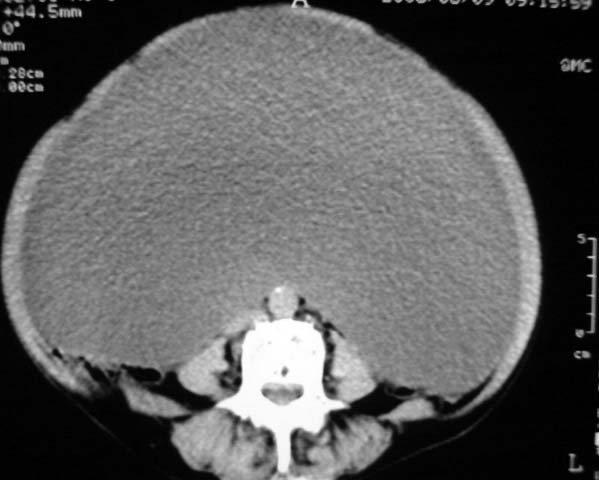

女,75岁,腹部胀大半年余,无其他症状。

考虑来源与卵巢的巨大囊腺瘤或囊肿。

真是腹大如牛,考虑卵巢巨大囊腺瘤或囊肿。

考虑来源卵巢巨大黏液性囊腺瘤。